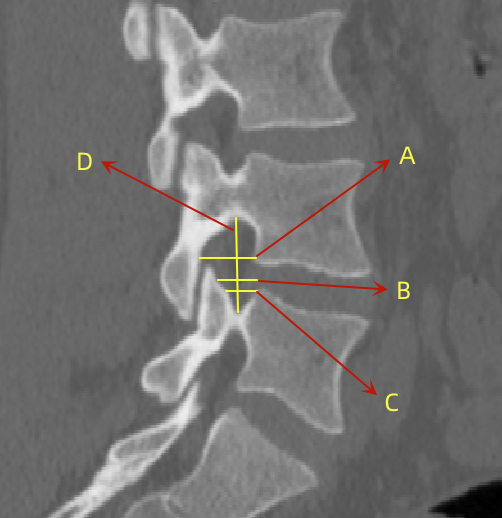

2�����、通过术前CT测量L4-5节段手术部位的(1)上位椎体后下角水平方向到关节突关节的距离(A)��;(2)纤维环后缘的中点水平方向到关节突关节的距离(B)���;(3)下位椎体后上角水平到关节突的距离(C)��;(4)上位椎体的椎弓下切迹与下位椎体椎弓上切迹连线的距离(D)���,图 6����;(5)在手术节段的棘突矢状位CT层测量椎间隙高度(E)����,图 7�����;(6)在手术节段的关节突关节横截面CT层测量关节突间距离(F)����,图 8���,再通过术中及术后CT判断患者椎间孔成型级别���,将A-F测量数据与5级成型中的各级别成型进行相关性分析����。

图 6 A-D的测量方式 |